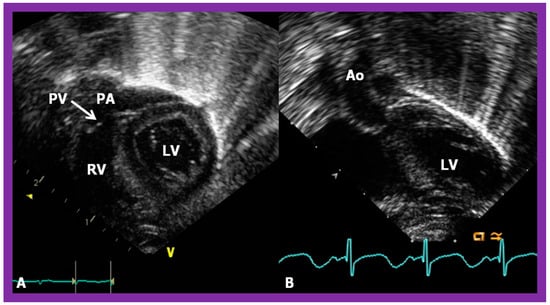

In theory, patients with cardiac malposition may have one (single) or two ventricles. The distinction between one and two ventricles is feasible by echocardiography (Figure 30) and angiography (Figure 31 and Figure 32).

Figure 30. Selected pictures from apical four-chamber echo views of two children, the first (A), who has two ventricles, and the second (B), who has one (single) ventricle (SV). The left atrium (LA), left ventricle (LV), right atrium (RA), and right ventricle (RV) are labeled. Reproduced from reference [4].

The ventricle to great artery (Ao and PA) relationship may be classified into 1. Concordant with the RV giving origin to the PA and the LV giving origin to the Ao, as seen in normal individuals (Figure 31 and Figure 46), 2. Discordant with A. the RV giving origin to the Ao and the LV giving origin to the PA, i.e., d-TGA in levocardia (Figure 35 and Figure 47) as well as d-TGA (d loop) in dextrocardia (Figure 36) and B. the morphologically RV giving origin to the Ao and the morphologically LV giving rise to the PA (l-TGA with l-loop) (Figure 40 and Figure 41), 3. double-outlet ventricle with A. both great vessels arising from the RV, i.e., double-outlet right ventricle (DORV) (Figure 48 and Figure 49) or B. both great arteries from the LV, i.e., double-outlet left ventricle (DOLV).

Figure 48. Echo frames from the parasternal long axis (A) and subcostal (B) views illustrating that both the aorta (Ao) and the pulmonary artery (PA) arise from the right ventricle (RV), i.e., double-outlet right ventricle. Note that the great vessels are normally related to each other. A ventricular septal defect (VSD) (vertical arrow) is also seen. The conal tissue (CT) is shown by thin arrows in (B). The vessel marked PA was traced further and demonstrated to subdivide into right and left pulmonary arteries. Left atrium (LA) and left ventricle (LV) are labeled. Modified from reference [43].

Figure 49. Echo images from the parasternal long axis (A) and subcostal (B) projections of a child with Taussig-Bing type of double-outlet right ventricle (with transposition of great vessels) illustrating that both the pulmonary artery (PA) and the aorta (Ao) arise from the right ventricle (RV). A large ventricular septal defect (VSD) and subaortic (SAT) and subpulmonary (SPT) tissues are also shown. The vessel marked PA was further traced and was demonstrated to divide into right and left PAs. Left atrium (LA) and left ventricle (LV) are labeled. Modified from reference [43].